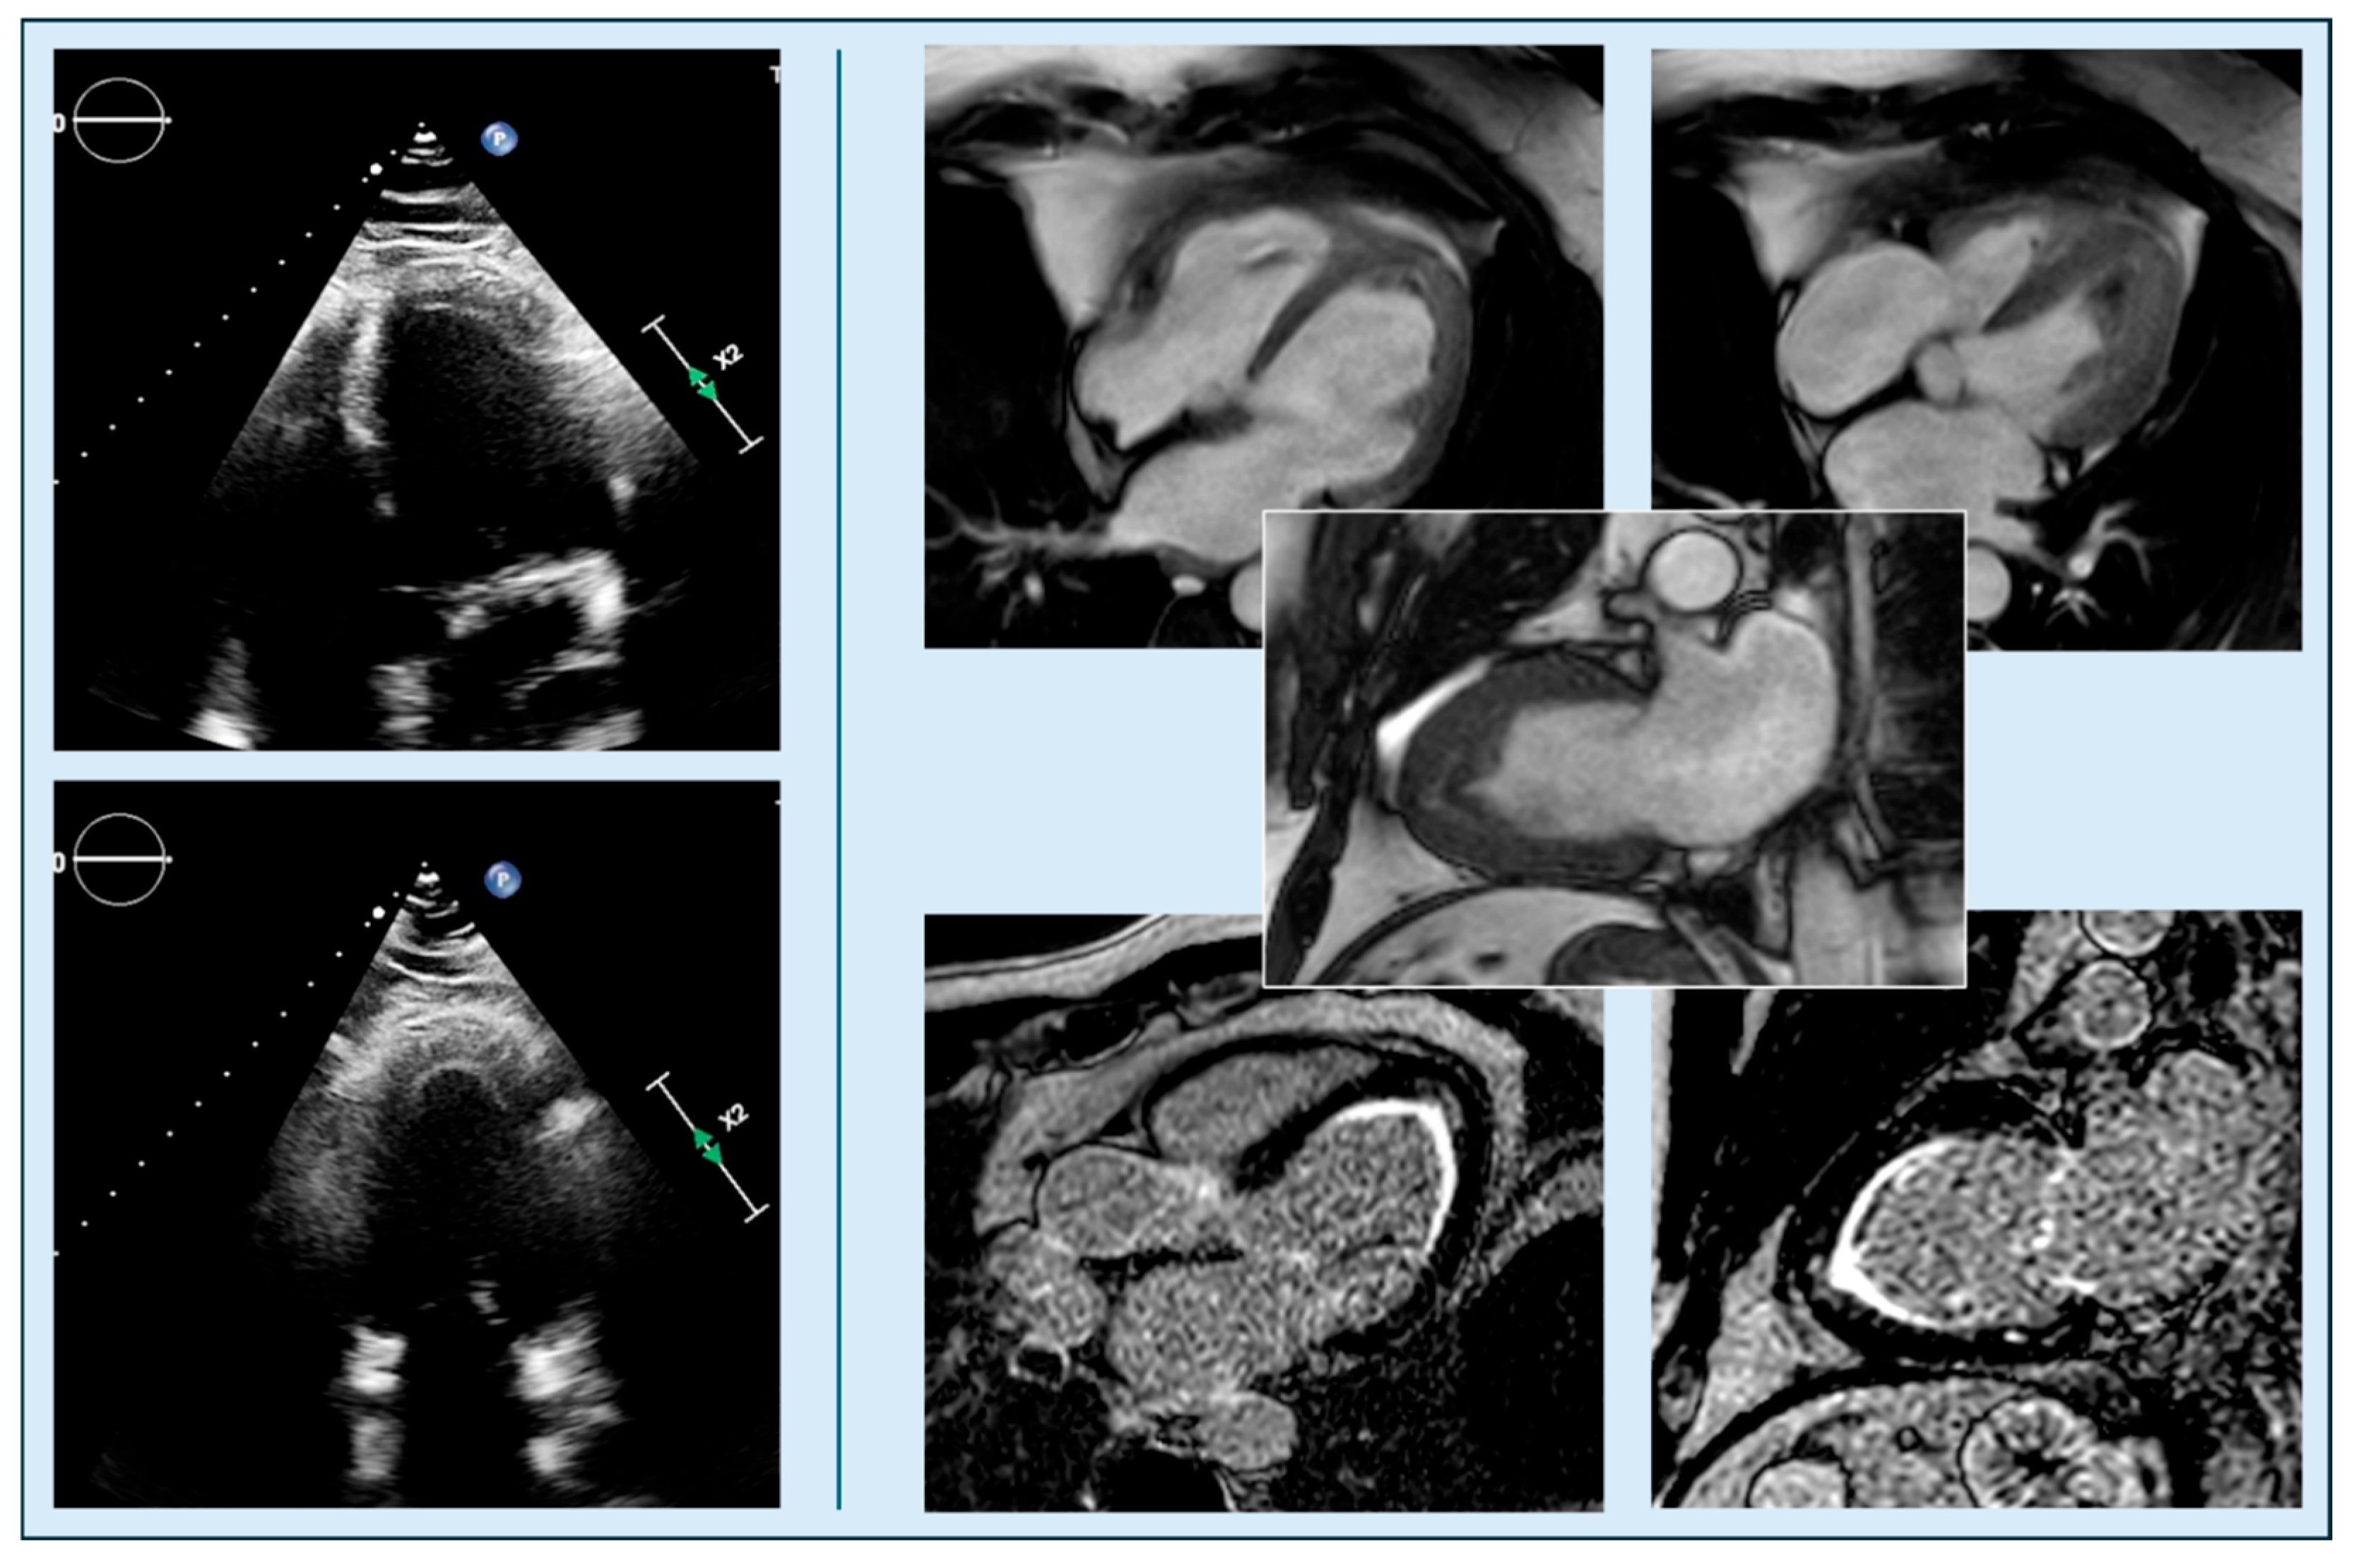

| Echocardiographic Detection | Good sensitivity, especially for septal hypertrophy; color-Doppler useful for LVOT obstruction | Often underestimated without contrast; up to 43% of apical aneurysms may be missed by TTE |

| Indexed apical obliteration length | TTE | >0.5 | ~180–190 ApHCM | Prognostic | Moderate | +++ | Kim 2016 [75] |

| Absolute apical obliteration | TTE | >20 mm | ~188 ApHCM | Specific | Moderate | +++ | Kim 2016 [75] |

| Apical cavity obliteration severity | TTE/CMRi | End-systolic closure | Echo/CMR cohorts | Prognostic | Moderate | +++ | Hamza 2025 [20] |

| Apical aneurysm detection | CMRi→TTE | Dyskinesis + scar | CMR aneurysm cohorts | Echo misses 43% | High | + | Hamza 2025 [20] |